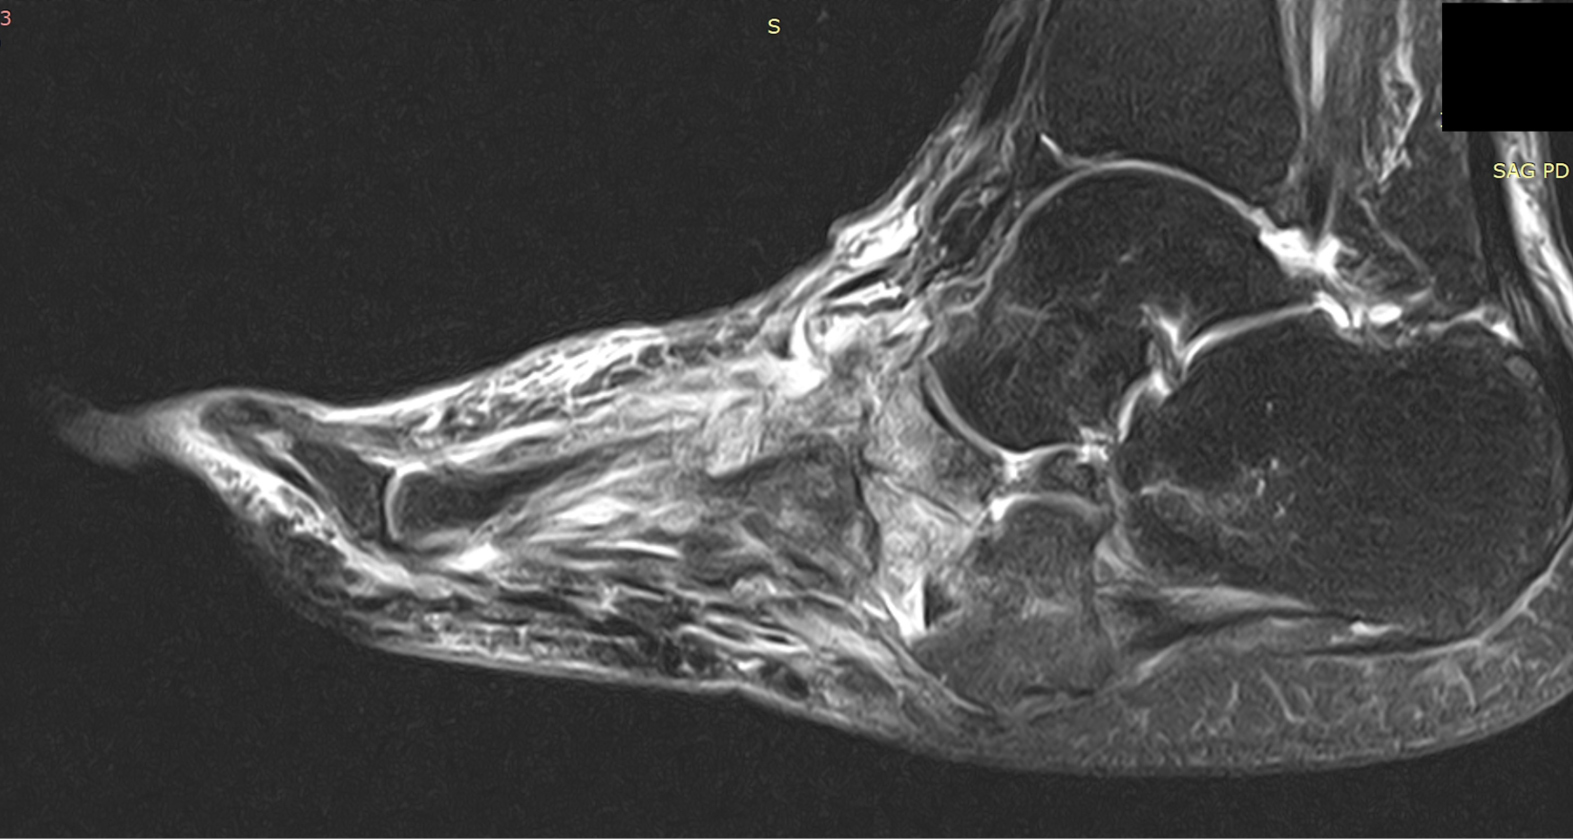

Рис. 8. Исходная МР-томограмма стопы. Режим жироподавления. Сагиттальный срез. Отек костей предплюсны, проксимальной головки II плюсневой кости, кубовидной, таранной, пяточной костей. Деструкция клиновидной кости.

Рис. 9. МР-томограмма стопы от 01.2019. Режим жироподавления. Сагиттальный срез. Отек кубовидной кости уменьшился, отек таранной и пяточной костей не определяется. В остальном – без динамики.

На рентгенограмме (начало октября 2018 г.) отмечается небольшая дислокация ладьевидной кости, нечеткость границ II, III клиновидных костей (возможное их разрушение), а также неизвестной давности экзостоз таранной кости (рис. 5, 6). В связи с неоднозначностью рентгенологических данных выполнена МР-томография. Выявлен отек костного мозга таранной, ладьевидной, кубовидной кости, деструкция клиновидных костей.

Сравнение рентгенологической картины и результатов МРТ продемонстрировало преимущество последнего. Так, в обоих случаях зона поражения по МРТ была больше, чем видимая на рентгенограмме. Кроме того, как показано на рис. 7, данные МРТ можно использовать для мониторирования эффективности лечения. Эти факты подтверждают преимущества применения МРТ в ведении пациентов с активной ДНОАП [8].